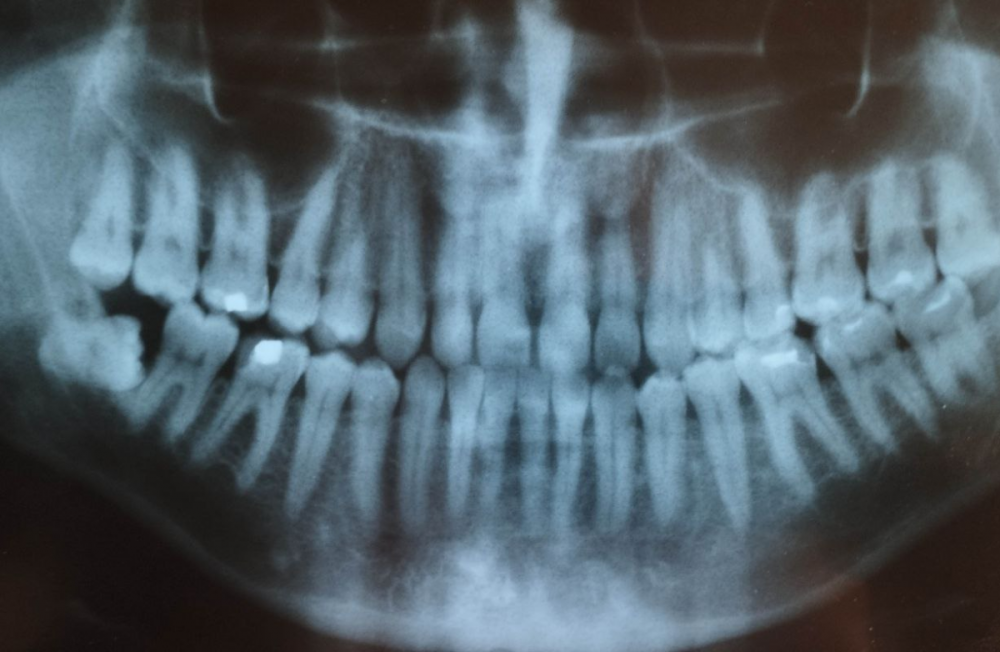

3убастик Опубликовано 27 мая, 2023 Поделиться Опубликовано 27 мая, 2023 Здравствуйте, подскажите как быть. Удалили сложную ретинированную восьмерку снизу, по причине что начала гноиться десна, зуб был в порядке. 10 дней лунка обрабатывалась ванночками из хлоргексидина после еды и еще несколько раз в промежутках. Спустя 10 дней, поняв что лунка не заживает, 10 дней в лунку закладывался левомеколь 3 раза в день на 20 минут на кусочке бинта (сам себе назначил по советам из интернета), убедившись что ничего не меняется на 23 день после удаления пошел к врачу, где был обнаружен небольшой альвеолит. Лунка была промыта хлоргексидином, врач вымыл остаток кровяного сгустка, назначил асепту, которая закладывалась в лунку по 2-3 раза в день. Через 3 дня был повторный осмотр с промыванием лунки, она оказалась чистой, продолжил закладывать асепту (14 дней), лунка особо не заживает до сих пор (сегодня 38 дней после операции и 15 дней как закладываю асепту), сделал повторный снимок, сходил еще раз на осмотр, врач сказал что стало немного получше, кюретаж не требуется, предложил продолжить до месяца использовать асепту и ждать пока затянется. В последние пару дней пару раз после закладывания асепты щипало в лунке минут по 10-15, до этого не было такого. Другой хирург посоветовал закладывать солкосерил, но меня смущает что через это лекарство может передаться болезнь Крейтцфельда-Якоба, которая аукнуться может через 5-15 лет и закончиться очень плачевно, плюс сам солкосерил сейчас стоит космических денег - за 5 г. тубу около 5 тысяч рублей. Подскажите, стоит ли использовать солкосерил, или может есть какие-то безопасные препараты для ускорения эпителизации? Прикладываю снимки до и после, плюс фото самой лунки, может кто на снимках что увидит почему не затягивается. И еще вопрос, на 7 зубе это что за вмятинка, отметил стрелкой на фото? Не может быть повреждения во время операции? Сверлили много... До удаления: После удаления: Лунка: Ссылка на комментарий